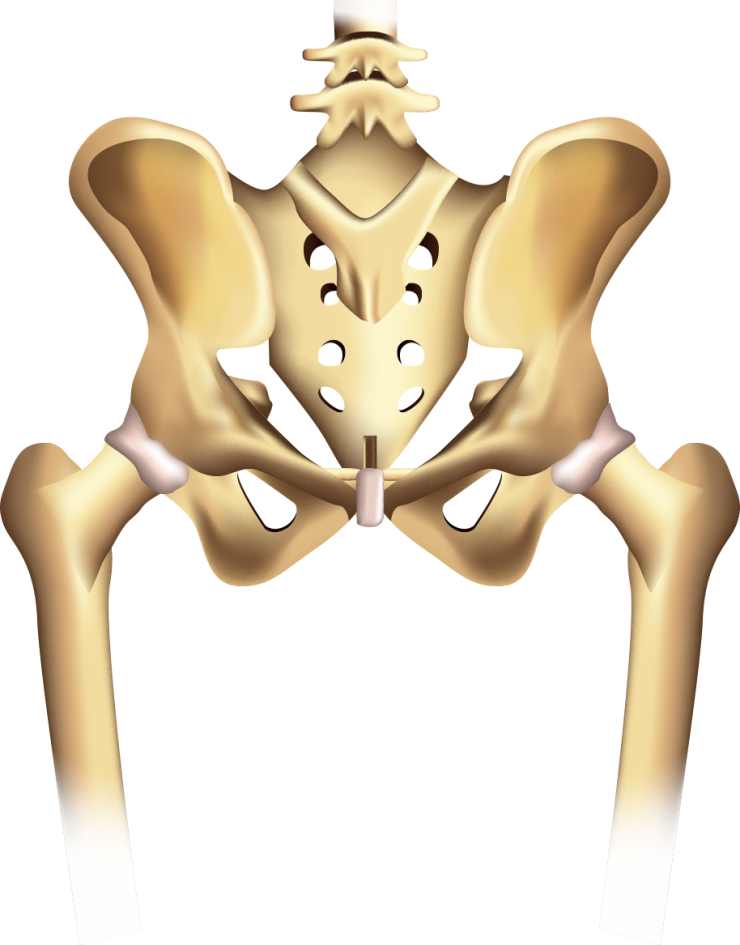

Структура позвоночника: сегменты и тазовые отделы в фотографиях